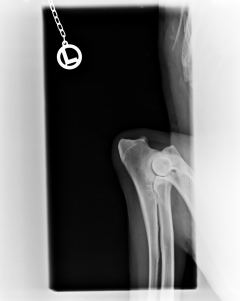

Bayou ist HD frei, ED frei und OCD frei.Beste Vorraussetzung für ein Deckrüde.

HD                                                           ED-Rechts                                         ED-Links                                                 OCD-rechts                                            OCD-links